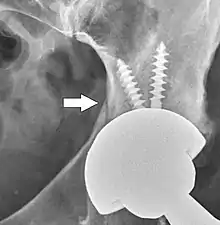

تجويف الحق الاصطناعي هو المكون الذي يعوض الحُق التالف. يتم في البداية إزالة الغضاريف والعظام من الحق التالف ويتم تثبيت تجويف الحق الاصطناعي في مكانه سواء عن طريق الاحتكاك أو باستخدام الإسمنت العظمي. تأتي بعض تجاويف الحُق الاصطناعية قطعة واحدة، في حين أن أخرى تأتي مقسمة إلى وحدات. تكون التجاويف الحقية ذات القطعة الواحدة مصنوعة إما من البولي إيثيلين عالي الوزن الجزيئي أو من المعدن، كما يكون سطحها المفصلي مشكلا على السطح الداخلي للتجويف ولا تعتمد على آلية القفل لتثبيت البطانة في مكانها. يتم لصق تجويف البولي إيثيلين ذي القطعة الواحدة في مكانه بينما يتم تثبيت التجويف المعدني في مكانه بواسطة كساء معدني على الجزء الخارجي من الحق. تتكون تجاويف الحق المقسمة لوحدات أساسا من قطعتين، غلاف وبطانة. الغلاف مصنوع من المعدن. حيث يحتوي الجزء الخارجي منه على كساء مسامي بينما يحتوي الجزء الداخلي على آلية قفل مصممة لتثبيت البطانة.هناك نوعان من الكساء المسامي المستخدم لتشكيل احتكاك مناسب هما الخرز اللملبد والتصميم المعدني الرغوي لتقليد ترابيق العظم الإسفنجي ويتأثر الثبات الأولي بقوة التوسيع والإيلاج.[10] يتحقق التثبيت الدائم عندما ينمو العظم على الطبقة المسامية أو داخلها. يمكن استخدام البراغي لتأخير انزلاق تجويف الحق عن العظم لتوفير مزيد من التثبيت. توضع بطانات البولي إيثيلين داخل الغلاف الحقي المزروع ويتم وصلها بآلية قفل حاصة؛ تثبت البطانات السيراميكيو والمعدنية بمصتدقة مورس.

يتم بعد الجراحة، إجراء تصوير الشعاعي لمنطقة المفصل المزروع وذلك للتأكد من نجاح العملية وضمان التكوين المناسب للأطراف الاصطناعية للورك. يؤثر اتجاه تجويف الحق المزروع على نطاق حركة الساق، كما يعد أيضا عاملا محددا لإمكانية حدوث خطر الخلع من عدمه.[31] لهذا الغرض، يتم اللجوء لإجراء قياسات خاصة لمقارنتها بالقيم الطبيعية. من بين أهم هذه القياسات نجد مثلا ميلان الحق ودرجة إنقلابه إلى الأمام بالنسبة للمستوى الإكليلي والمستوى السهمي على التوالي.

ميل الحق.[32] يتم قياس هذا المؤشر بالنسبة لصورة أمامية مرجعية تم التقاطها لورك المريض باستعمال الأشعة السينية. زاوية الميل هذه هي الزاوية التي يشكلها تقاطع الخط الهامشي الجانبي والأوسط لمكون الحق من جهة والخط المماسي للحواف السفلية لعظم الإسك من جهة أخرى.[32]

انقلاب الحق نحو الأمام.[33] يتم قياس هذا المؤشر بالرجوع إلى صورة شعاعية جانبية لمنطقة المفصل، حيث تمثل زاوية انقلاب المفصل نحو الأمام تلك الزاوية التي تقع بين المستوى الأفقي والخط المار عبر الهوامش الأمامية والخلفية لتجويف الحق المزروع.[33]